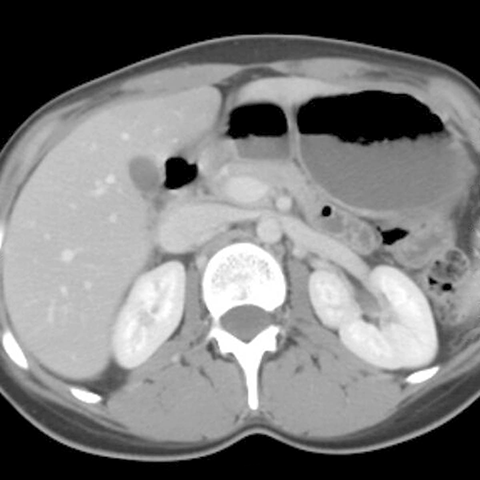

Normal kidney, axial image [3 of 9]